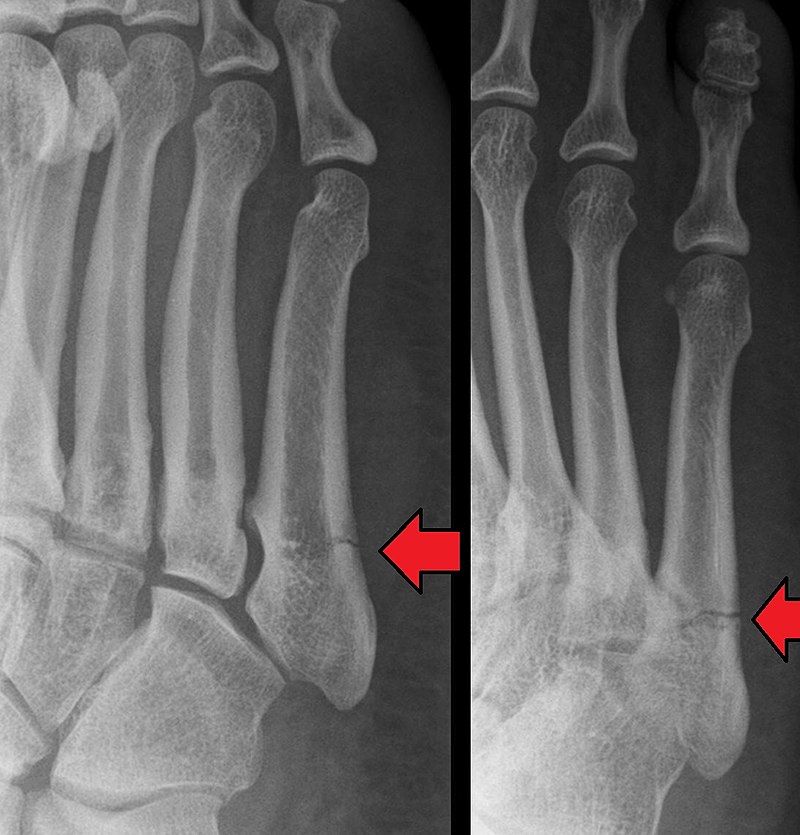

Xray of human feet. Normal radiography of the foot, medical diagnostics, traumatology and

Xray of human feet. Normal radiography of the foot, medical diagnostics, traumatology and Types Of Foot X Rays The air in the lungs shows up as black. Box 2.1 types of radiographs. The image displays the soft tissues and bones of your foot. Fat and muscle appear as shades of gray. These bones include your ankle bones (tarsal bones),. These are listed in box 2.1. In total, there are four types of radiographs. These bones include the tarsal. Types Of Foot X Rays.